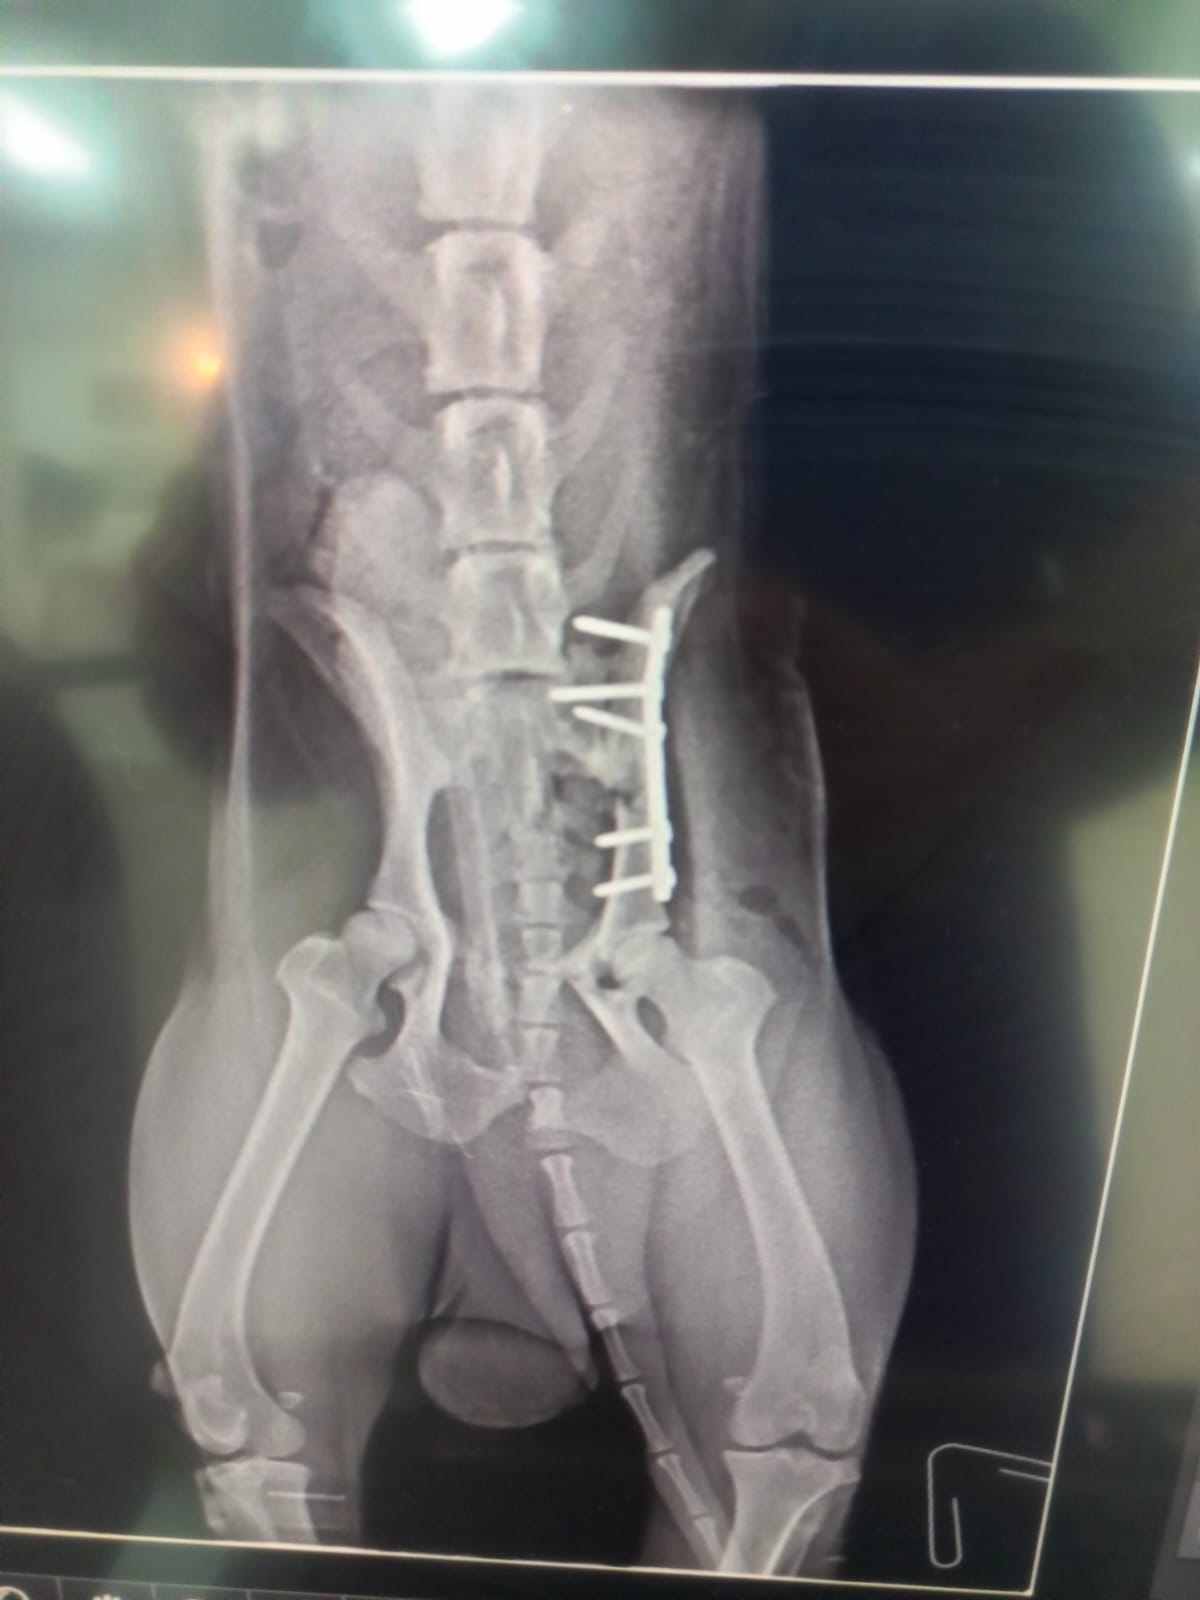

Sweet Artic was rescued after being hit by not one but two cars ! Artic was barely done with the first hit and run when he was struck again… We didn’t even think about it, we knew that we had to act. Artic was rushed to the nearest animal hospital where he received all the necessary treatment to be stabilized. His xrays show no break to his limbs however his pelvis was crushed. His head trauma was very apparent, his nose bleed didn’t stop until the next day of his rescue… He was on IV, pain medication and under constant observation… Two days later he was stable enough to undergo surgery. Today, he’s ready to be adopted. He’s a bit shy at first, he’s calm and needs a stable and calm environment , no children. He’s good with other dogs. DOB: 01/01/2023

ARTIC Photo Gallery